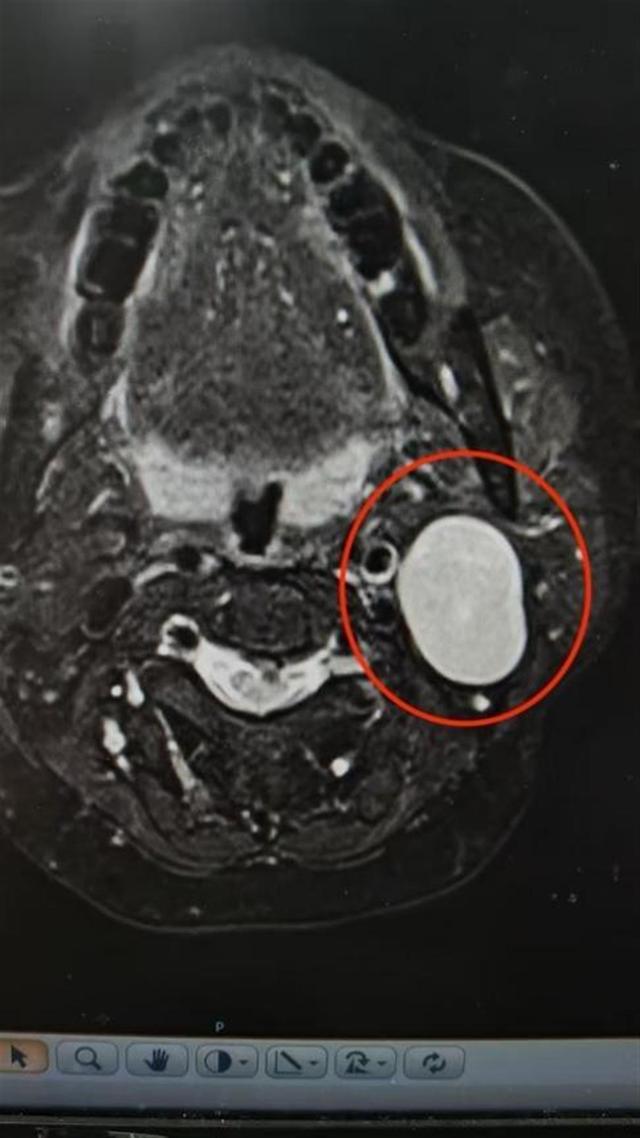

孙奶奶术前影像图

家住武汉的孙婆婆偶然发现自己两边脸不对称,左边脸比右边脸长胖了些,但并没有太在意。女儿却对此十分重视,立即带她到武汉大学中南医院口腔医学中心检查。通过初步检查,口腔颌面外科程波主任发现,患者左侧腮腺区有一枚肿块,并且体积还不小。孙婆婆惊讶道:“我以为是最近长胖了,再加上年纪大,皮肤松弛,就没当回事儿,听女儿的话才来的,没想到竟然是个肿块。”

程波解释:“多数腮腺区肿物的首发症状就是耳垂下方或耳垂周围的无痛性肿块缓慢增大,一开始症状不明显,因此容易被忽视。如果肿物的位置比较深,往往发现的时候,肿瘤已经很大了。”经过进一步影像学检查,孙婆婆被确诊为腮腺肿瘤,需手术治疗。